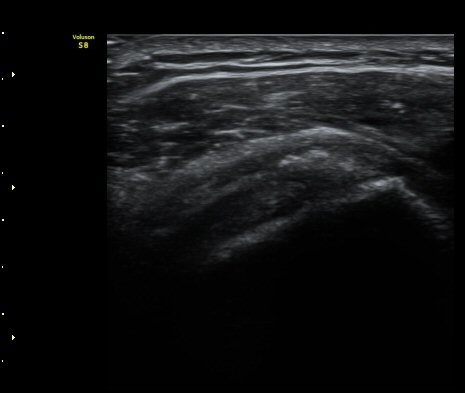

ȸÀü±Ù°³°£°Ý(rotator cuff interval) Ⱦ´Ü¸é°Ë»ç¿¡¼­ Á¡¾×³¶¸Å ¼ö¾× Àú·ù°¡ °üÂûµÈ´Ù(±×¸² 1).